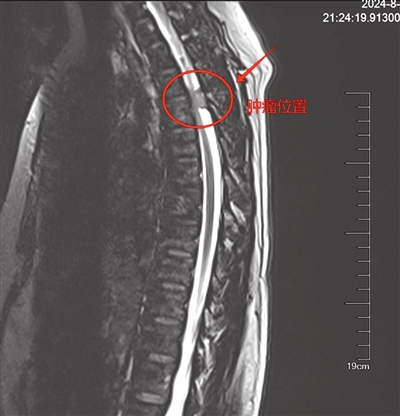

椎管内肿瘤指生长于椎管内的肿瘤,又称脊髓肿瘤。通讯员 姜鑫 摄

本报讯(记者邓婉莹 见习记者陶斯祎 通讯员姜鑫)一名女性患者因胸椎椎管内长出肿瘤,压迫神经,导致大小便功能失常,无法正常行走,只能卧病在床,处于半瘫痪状态,严重影响生活质量。该患者近日到中山五院脊柱外科就诊。

该院脊柱外科吕海主任团队对患者进行了问诊及初步检查,确诊为胸椎椎管内肿瘤症状,可能会导致全瘫,建议采用显微镜下切除胸椎椎管肿瘤手术。吕海表示,该手术属于微创手术,在避开患者重要的血管与神经组织的基础上,逐步分离并完整切除肿瘤,最大限度地减少对周围正常组织的损伤。术后,患者大小便功能逐渐正常,能重新站立并行走,现已恢复正常生活。